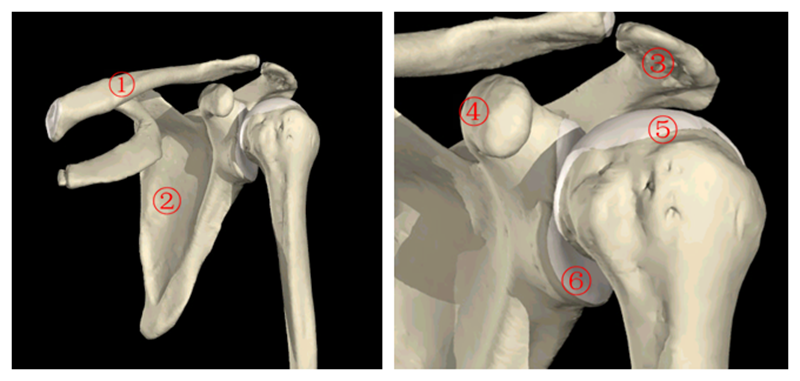

肩关节解剖结构

肩袖是由冈上肌、冈下肌、肩胛下肌及小圆肌的腱性部分组成的鞘状结构。它包绕盂肱关节、肱骨头、关节囊,形成近似袖套样肌样结构,具有保持肱盂关节稳定,维持上臂各种姿势和完成各种运动的功能。

图1肩关节骨解剖 1.锁骨2.肩胛骨3.肩峰4.喙突5.肱骨头6.关节盂

图2 肩袖解剖1.肩胛下肌2.冈上肌3.冈下肌4.小圆肌